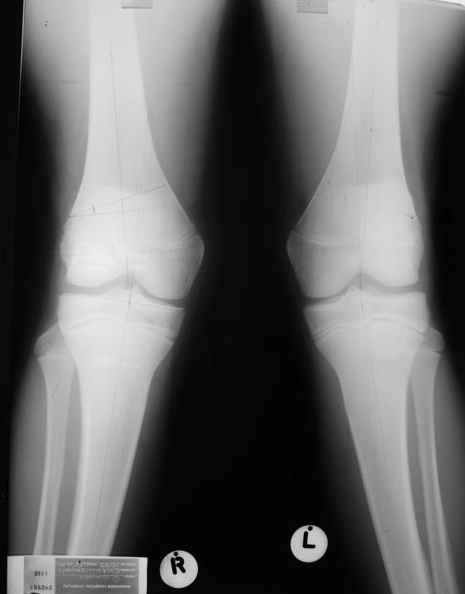

Как вариант решения прогрессирующей вальгусной деформации коленного сустава я бы предложил косую остеотомию дистального отдела бедра с фиксацией пластиной и компрессирующим винтом.

Взгляните на снимки , может быть это вам поможет.

Около 5 лет применяю этот тип дистальной остеотомии бедра для коррекции механической оси Н/К ( более 20 случаев) - достаточно эффективная операция.